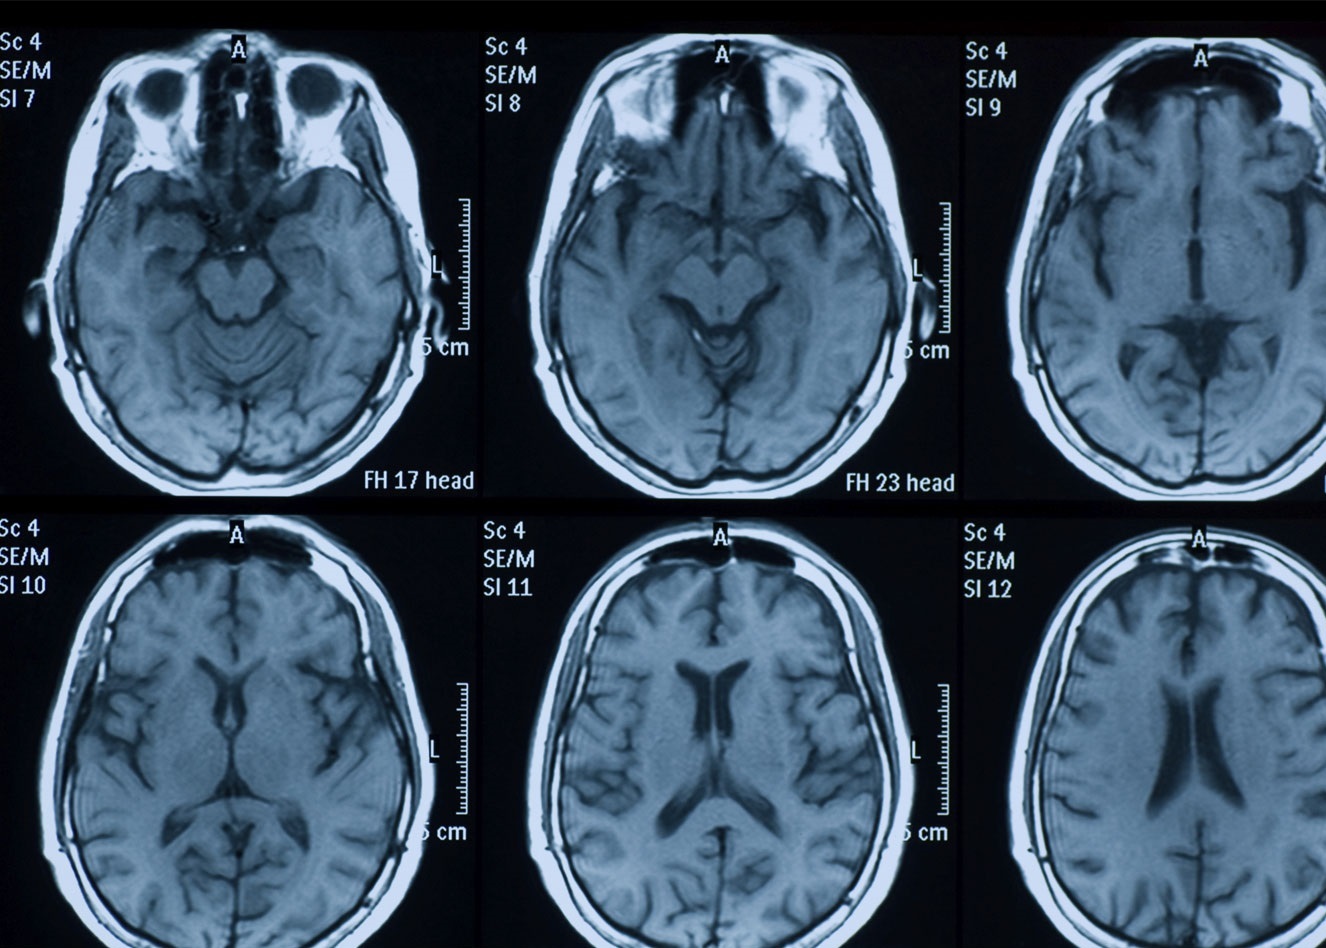

پیش از این، این نوع تصویربرداری تنها با دستگاههای تصویربرداری رزونانس مغناطیسی کاربردی (fMRI) انجام میشد که از امواج رادیویی و میدانهای مغناطیسی که ۱۰۰ هزار برابر قویتر از میدان مغناطیسی زمین هستند، برای نظارت بر سطح اکسیژن خون استفاده میکردند.

این دستگاهها بسیار گران هستند و هرکدام تا چند میلیون دلار قیمت دارند. نکته منفی دیگر این است که میدانهای مغناطیسی شدید ایجاد شده توسط دستگاه نیاز به اقدامات احتیاطی خاصی دارد، زیرا اجسام حاوی آهن مانند برخی از ابزارهای پزشکی و همچنین ایمپلنتهای جراحی با نیروی زیادی توسط دستگاه کشیده میشوند. همچنین برای استفاده از دستگاه MRI در هنگام تصویربرداری باید یک لوله باریک در داخل بدن بیمار قرار داده شود که ممکن است برای افراد مبتلا به کلاستروفوبیا ناراحت کننده باشد.